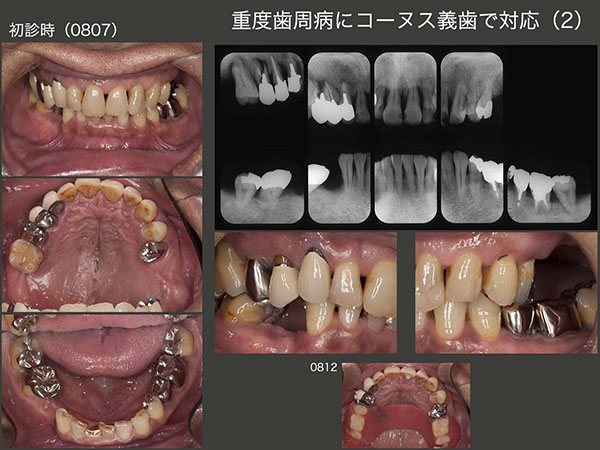

4.重度歯周病にコーヌス義歯で対応(2)

2008年7月初診,58歳男性.他院で上顎はすべて抜歯し,総義歯にするという説明を受けた.何とか歯を残せないか?とのことで当院を受診した.

まず,9月に保存不可能な右上5,6を抜歯し,即時義歯を装着した.(スライド写真は12月の状態.大連結装置の違和感が強くあまり使用していない.) 歯周ポケットは,右上2〜4および左上1は最深部で8〜10mm存在した.また1日1箱のたばこを吸っていた.まず,歯周ポケットの深い左上1,右上2を抜髄し,左上1,右上2〜4の自然挺出を行った.左上1は約1年経過を観察したが,歯周ポケットが改善せず抜去した.右上1〜4は歯周外科処置を行った.左上2は形成量が多かったためか歯髄炎を起こし,やむを得ず抜髄した.